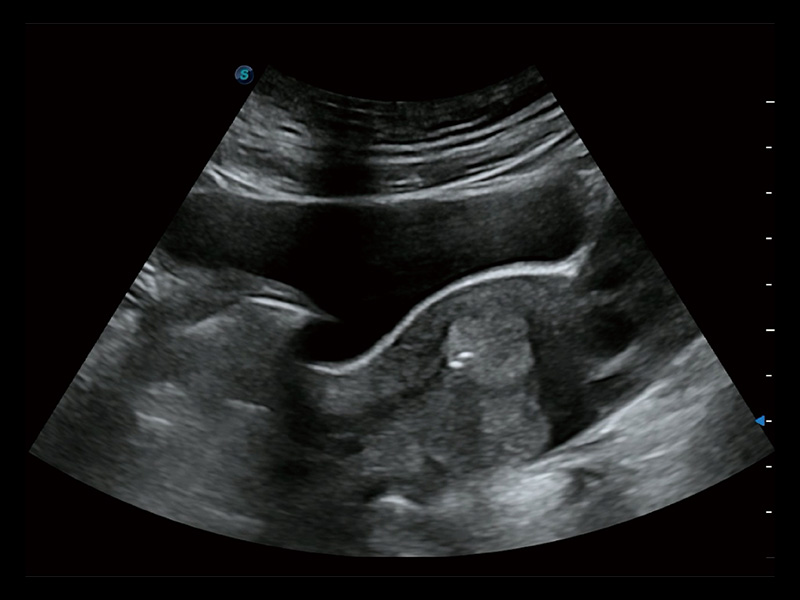

超声引导下胚胎移植